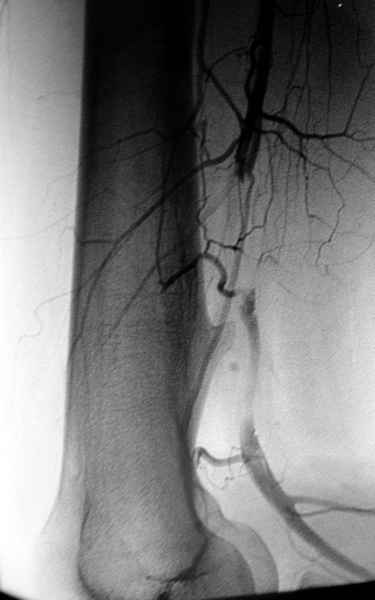

Ангиография подтвердила васкулярную аневризму в

результате давления экзостозом. Совместно с сосудистым хирургом была проведена плоскостная резекция с дальнейщим восстановлением сосуда венозным графтом.